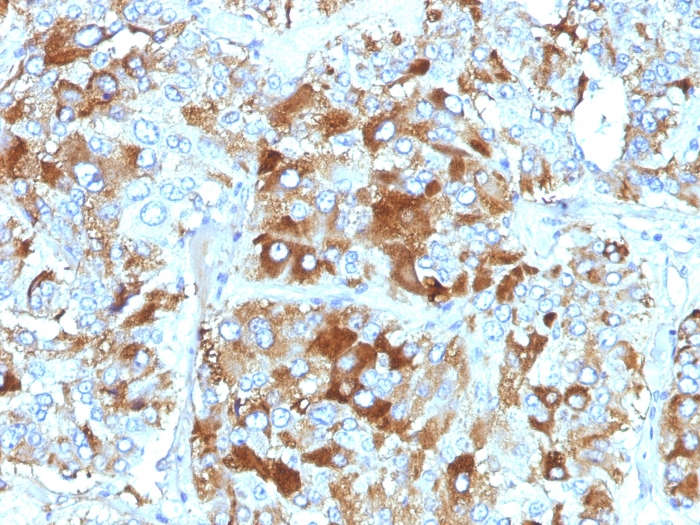

Formalin-fixed, paraffin-embedded human Pancreas stained with Chromogranin A Mouse Monoclonal Antibody (CHGA/765).

Chromogranin A is present in neuroendocrine cells throughout the body, including the neuroendocrine cells of the large and small intestine, adrenal medulla and pancreatic islets. It is an excellent marker for carcinoid tumors, pheochromocytomas, paragangliomas, and other neuroendocrine tumors. Co-expression of chromogranin A and neuron specific enolase (NSE) is common in neuroendocrine neoplasms. Reportedly, co-expression of certain keratins and chromogranin indicates neuroendocrine lineage. The presence of strong anti-chromogranin staining and absence of anti-keratin staining should raise the possibility of paraganglioma. The co-expression of chromogranin and NSE is typical of neuroendocrine neoplasms. Most pituitary adenomas and prolactinomas readily express chromogranin.